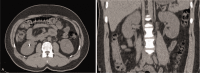

Outcomes: The patient's complaints disappeared on the fourth day of treatment. Macroscopic and microscopic hematuria was not seen in the following days. Follow-up CT was done 3 months after discharge and showed normal left renal pelvis without hyperdenosis. Follow-up CT was performed 3 months after discharge and presented normal left renal pelvis with no hyperdense lesion.